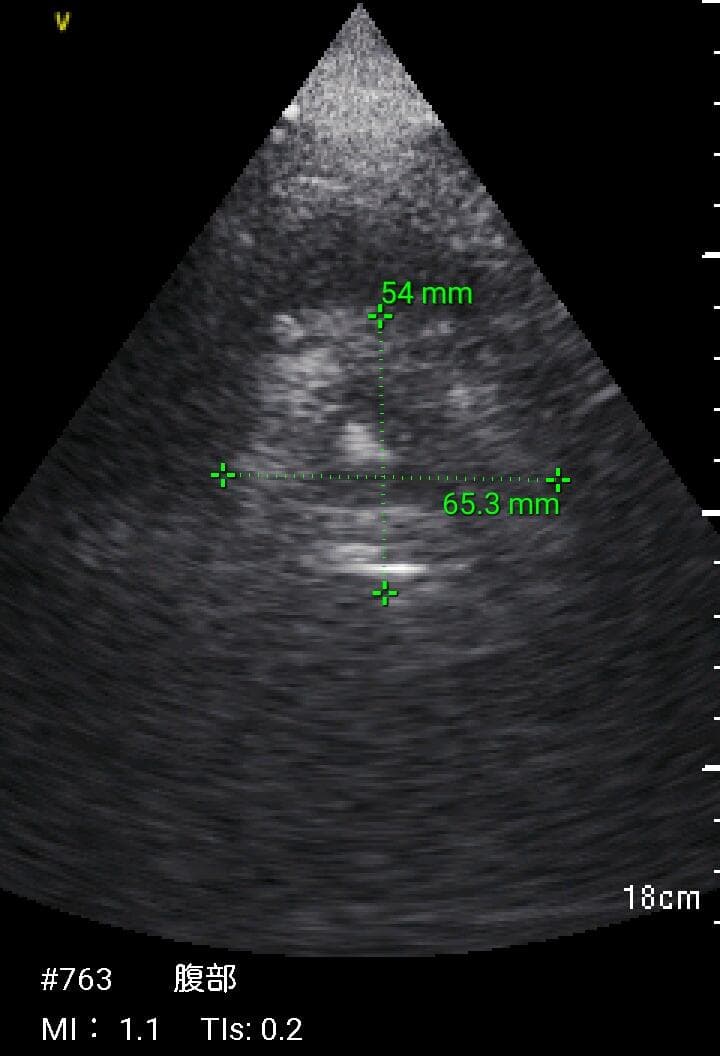

おわかりになる方のみの購入をお願いいたします実際に実施した写真をあげました正常肝臓、胆石症、頸動脈プラーク、同じく頸動脈プラーク、Mrの収縮期、同じくM弁の開放期とA弁の開放期、腹部大動脈瘤、正常の頸動脈、甲状腺右葉の結節、前立腺肥大画像の描出は条件によりますがご検討をお願いいたします経年変化、使用に伴うスレや傷などがあります機能に問題はありませんスキャンは心血管、腹部、体表に対応します外部接続端子のカバーが一部壊れていますが蓋は閉まりますバッテリーはフル充電されますが劣化はあると思います医療用モニタリング機器 Vscan Extend、GE- モデル名: Vscan Extend- ブランド: GE- 色: ホワイト- 機能: 医療用モニタリング機器ご覧いただきありがとうございます。。[新品未使用品]KT TAPE ブラック 25cm プレカット 150枚入